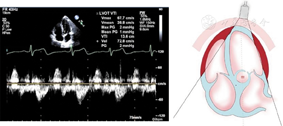

(2)心尖五腔心切面(图20图21)

心尖五腔切面引导脉冲波多普勒取样主动脉瓣瓣环收缩期血流速度峰值与时间速度积分测量

图20

心尖五腔切面引导脉冲波多普勒取样左心室流出道收缩期血流速度峰值与时间速度积分测量方法,左心室流出道收缩期速度和时间速度积分应在主动脉瓣下1 cm处测量,取样线应当尽量与左心室流出道长轴平行

图21